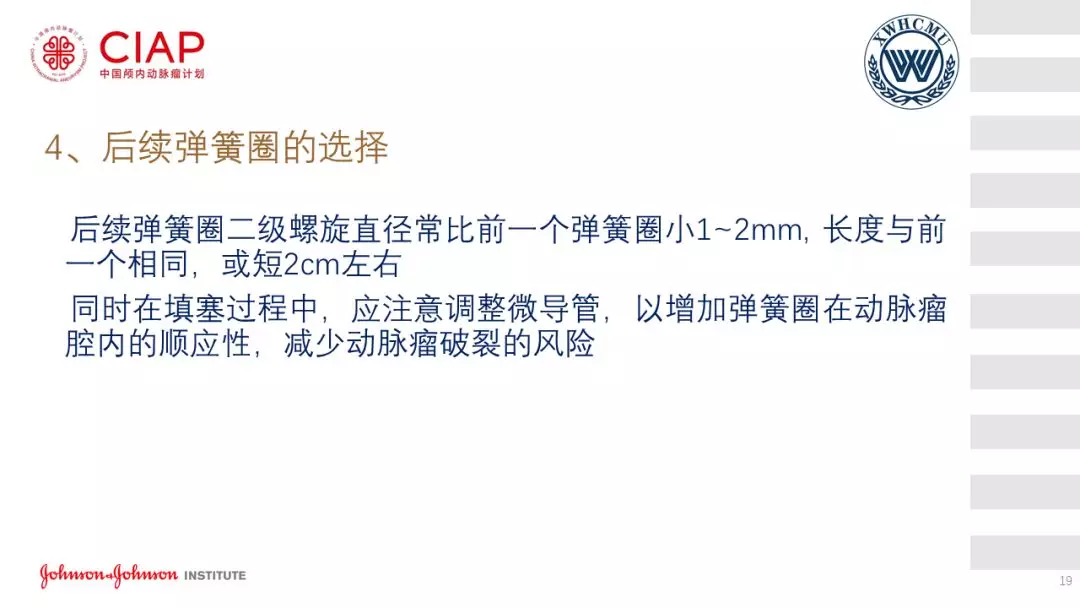

张鹏教授:不同辅助方法下栓塞动脉瘤弹簧圈的选择